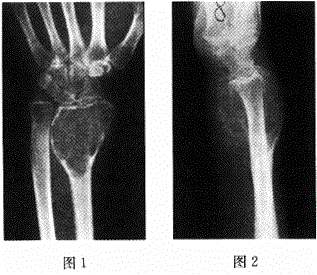

男,32岁。右腕部疼痛3个月。体检:右侧桡骨远端肿胀,有压痛。体温正常,实验室检查未见异常。

男,32岁。右腕部疼痛3个月。体检:右侧桡骨远端肿胀,有压痛。体温正常,实验室检查未见异常。最可能的诊断是

A骨巨细胞瘤

B骨肉瘤

C骨软骨瘤

D软骨瘤

E骨血管瘤